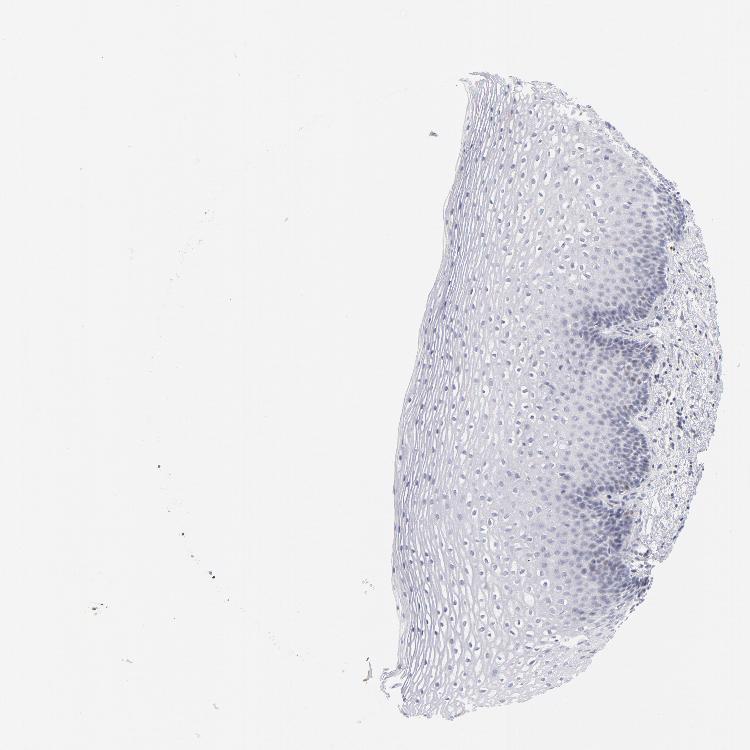

ESOPHAGUS - Antibody stainingi

Antibody staining in the annotated cell types in the current human tissue is reported as not detected, low, medium, or high, based on conventional immunohistochemistry profiling in selected tissues. This score is based on the combination of the staining intensity and fraction of stained cells.

Each image is clickable and will lead to virtual microscopy that enables deeper exploration of all samples and also displays staining intensity scores, fraction scores and subcellular localization as well as patient and tissue information for each sample.

Antibody HPA045168Antibody CAB000147Antibody CAB003839Antibody CAB003840Antibody CAB075726Antibody CAB075727

Squamous epithelial cells HighNot detectedNot detectedMediumMediumHigh